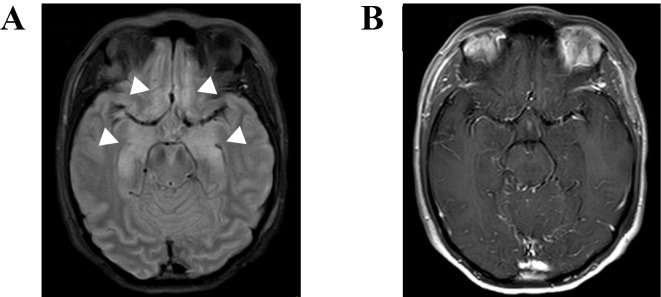

Primary cutaneous CD8-positive aggressive epidermotropic cytotoxic T-cell lymphoma (PCAE-CTL) is a rare subtype of cutaneous T-cell lymphoma with a poor prognosis. We herein report a case of PCAE-CTL accompanied by anti-Ma2 antibody-positive paraneoplastic encephalitis. A 33-year-old woman with erythema and disturbance of consciousness was diagnosed with PCAE-CTL by a skin biopsy. Head magnetic resonance imaging revealed bilateral medial temporal lobe hyperintensity, and anti-Ma2 antibody in the cerebrospinal fluid was positive. She was diagnosed with concurrent anti-Ma2 antibody-positive paraneoplastic encephalitis. In cases of lymphoma with brain lesions, invasion of the central nervous system by lymphoma and paraneoplastic encephalitis should be considered.

原发性皮肤cd8阳性侵袭性表皮细胞毒性t细胞淋巴瘤(PCAE-CTL)是一种罕见的皮肤t细胞淋巴瘤亚型,预后较差。我们在此报告一例PCAE-CTL伴抗ma2抗体阳性副肿瘤脑炎。一名33岁女性,红斑和意识障碍,通过皮肤活检诊断为PCAE-CTL。头部磁共振示双侧内侧颞叶高信号,脑脊液抗ma2抗体阳性。她被诊断为并发抗ma2抗体阳性副肿瘤脑炎。在淋巴瘤伴脑病变的病例中,应考虑淋巴瘤和副肿瘤脑炎对中枢神经系统的侵犯。